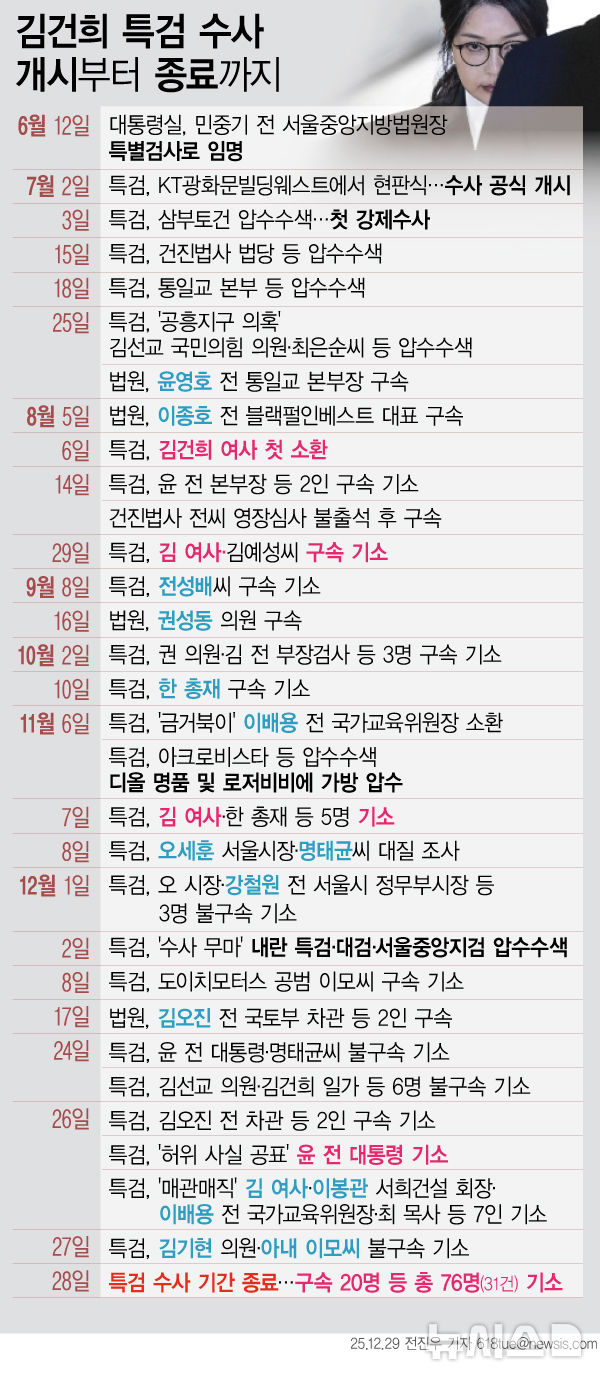

[서울=뉴시스] 미국 콜로라도대 암센터 폐암 프로그램을 이끄는 로스 카미지(58) 박사가 폐암 진단을 받은 사실을 뒤늦게 공개했다. 사진은 카미지 박사의 모습. (사진 = CBS콜로라도 캡처) 2025.09.30. *재판매 및 DB 금지

[서울=뉴시스]이소원 인턴 기자 = 세계적인 폐암 치료 권위자가 자신도 폐암 말기 환자임을 뒤늦게 고백했다.

23일(현지시각) 미국 매체 CBS 콜로라도는 미국 콜로라도대 암센터 폐암 프로그램을 이끄는 로스 카미지(58) 박사가 "3년 전 폐암 진단을 받았다"며 투병 사실을 공개했다고 보도했다.

카미지 박사는 지난 20여 년간 표적 치료제 개발과 암 진행 과정을 연구하며 전 세계 수천 명의 환자들을 치료해 왔다. 그는 진단 이후에도 수십 년간 건강한 삶을 이어가는 환자들을 배출하며 폐암 치료 연구의 선구자로 평가받고 있다.

그러나 2022년 카미지 박사는 쌕쌕거리는 호흡과 어깨 통증으로 검사를 받던 중 4기 진행성 폐암 진단을 받았다. 당시 그는 단순한 천식이나 근육 손상 정도로 여겼지만, 불과 나흘 만에 불치 판정을 받게 됐다고 한다.

카미지 박사는 자신의 아이들과 환자들을 위해 투병 사실을 철저히 숨겨왔지만, 최근 연구와 치료에 직접적인 도움이 될 것으로 판단해 공개를 결심했다고 전했다. 그는 "암 진단이 곧 삶의 끝을 의미하지 않는다"면서 "일부 암은 만성 질환처럼 관리할 수 있다"라고 강조했다.

또한 평생 연구해 온 병에 자신도 걸리게 된 심정을 묻자 그는 "화가 나지 않는다. 오히려 영광스럽게 생각한다"며 "수많은 환자들의 입장이 돼 그들의 신발을 신어보는 특권을 얻은 것"이라고 답했다.

현재도 카미지 박사는 연구 현장에서 후학을 양성하며 환자들을 돕고 있는 것으로 알려졌다.